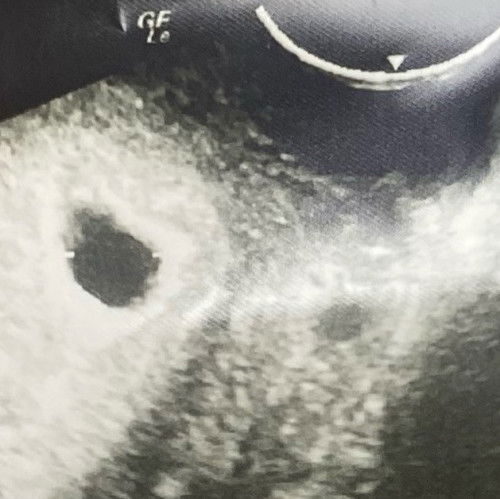

หมออัลตร้าซาวด์ผ่านช่องคลอด หมอบอกว่า อายุครรภ์ยังน้อยเลยอาจจะยังไม่เจอตัวน้อง คะ ตอนนี้กังวลใจ และเครียดมากๆเลยคะ เลือดมันไหล กระปริบกระปรอยออกมาคะ แต่ไม่เยอะคะ ไม่มีอาการปวดท้อง หรืออะไรเลยคะ วันที่ 19 นี้ไปฝากท้องแล้วคะ รู้สึกเครียดไม่รู้จะทำยังไงดีคะ #ท้องที่2 หมอไม่ได้บอกว่าจะมีภาวะที่จะแท้งคุกคามหรืออะไรเลยคะ หมอบอกว่า อาจจะเป็นการฝังตัวอ่อน คะ